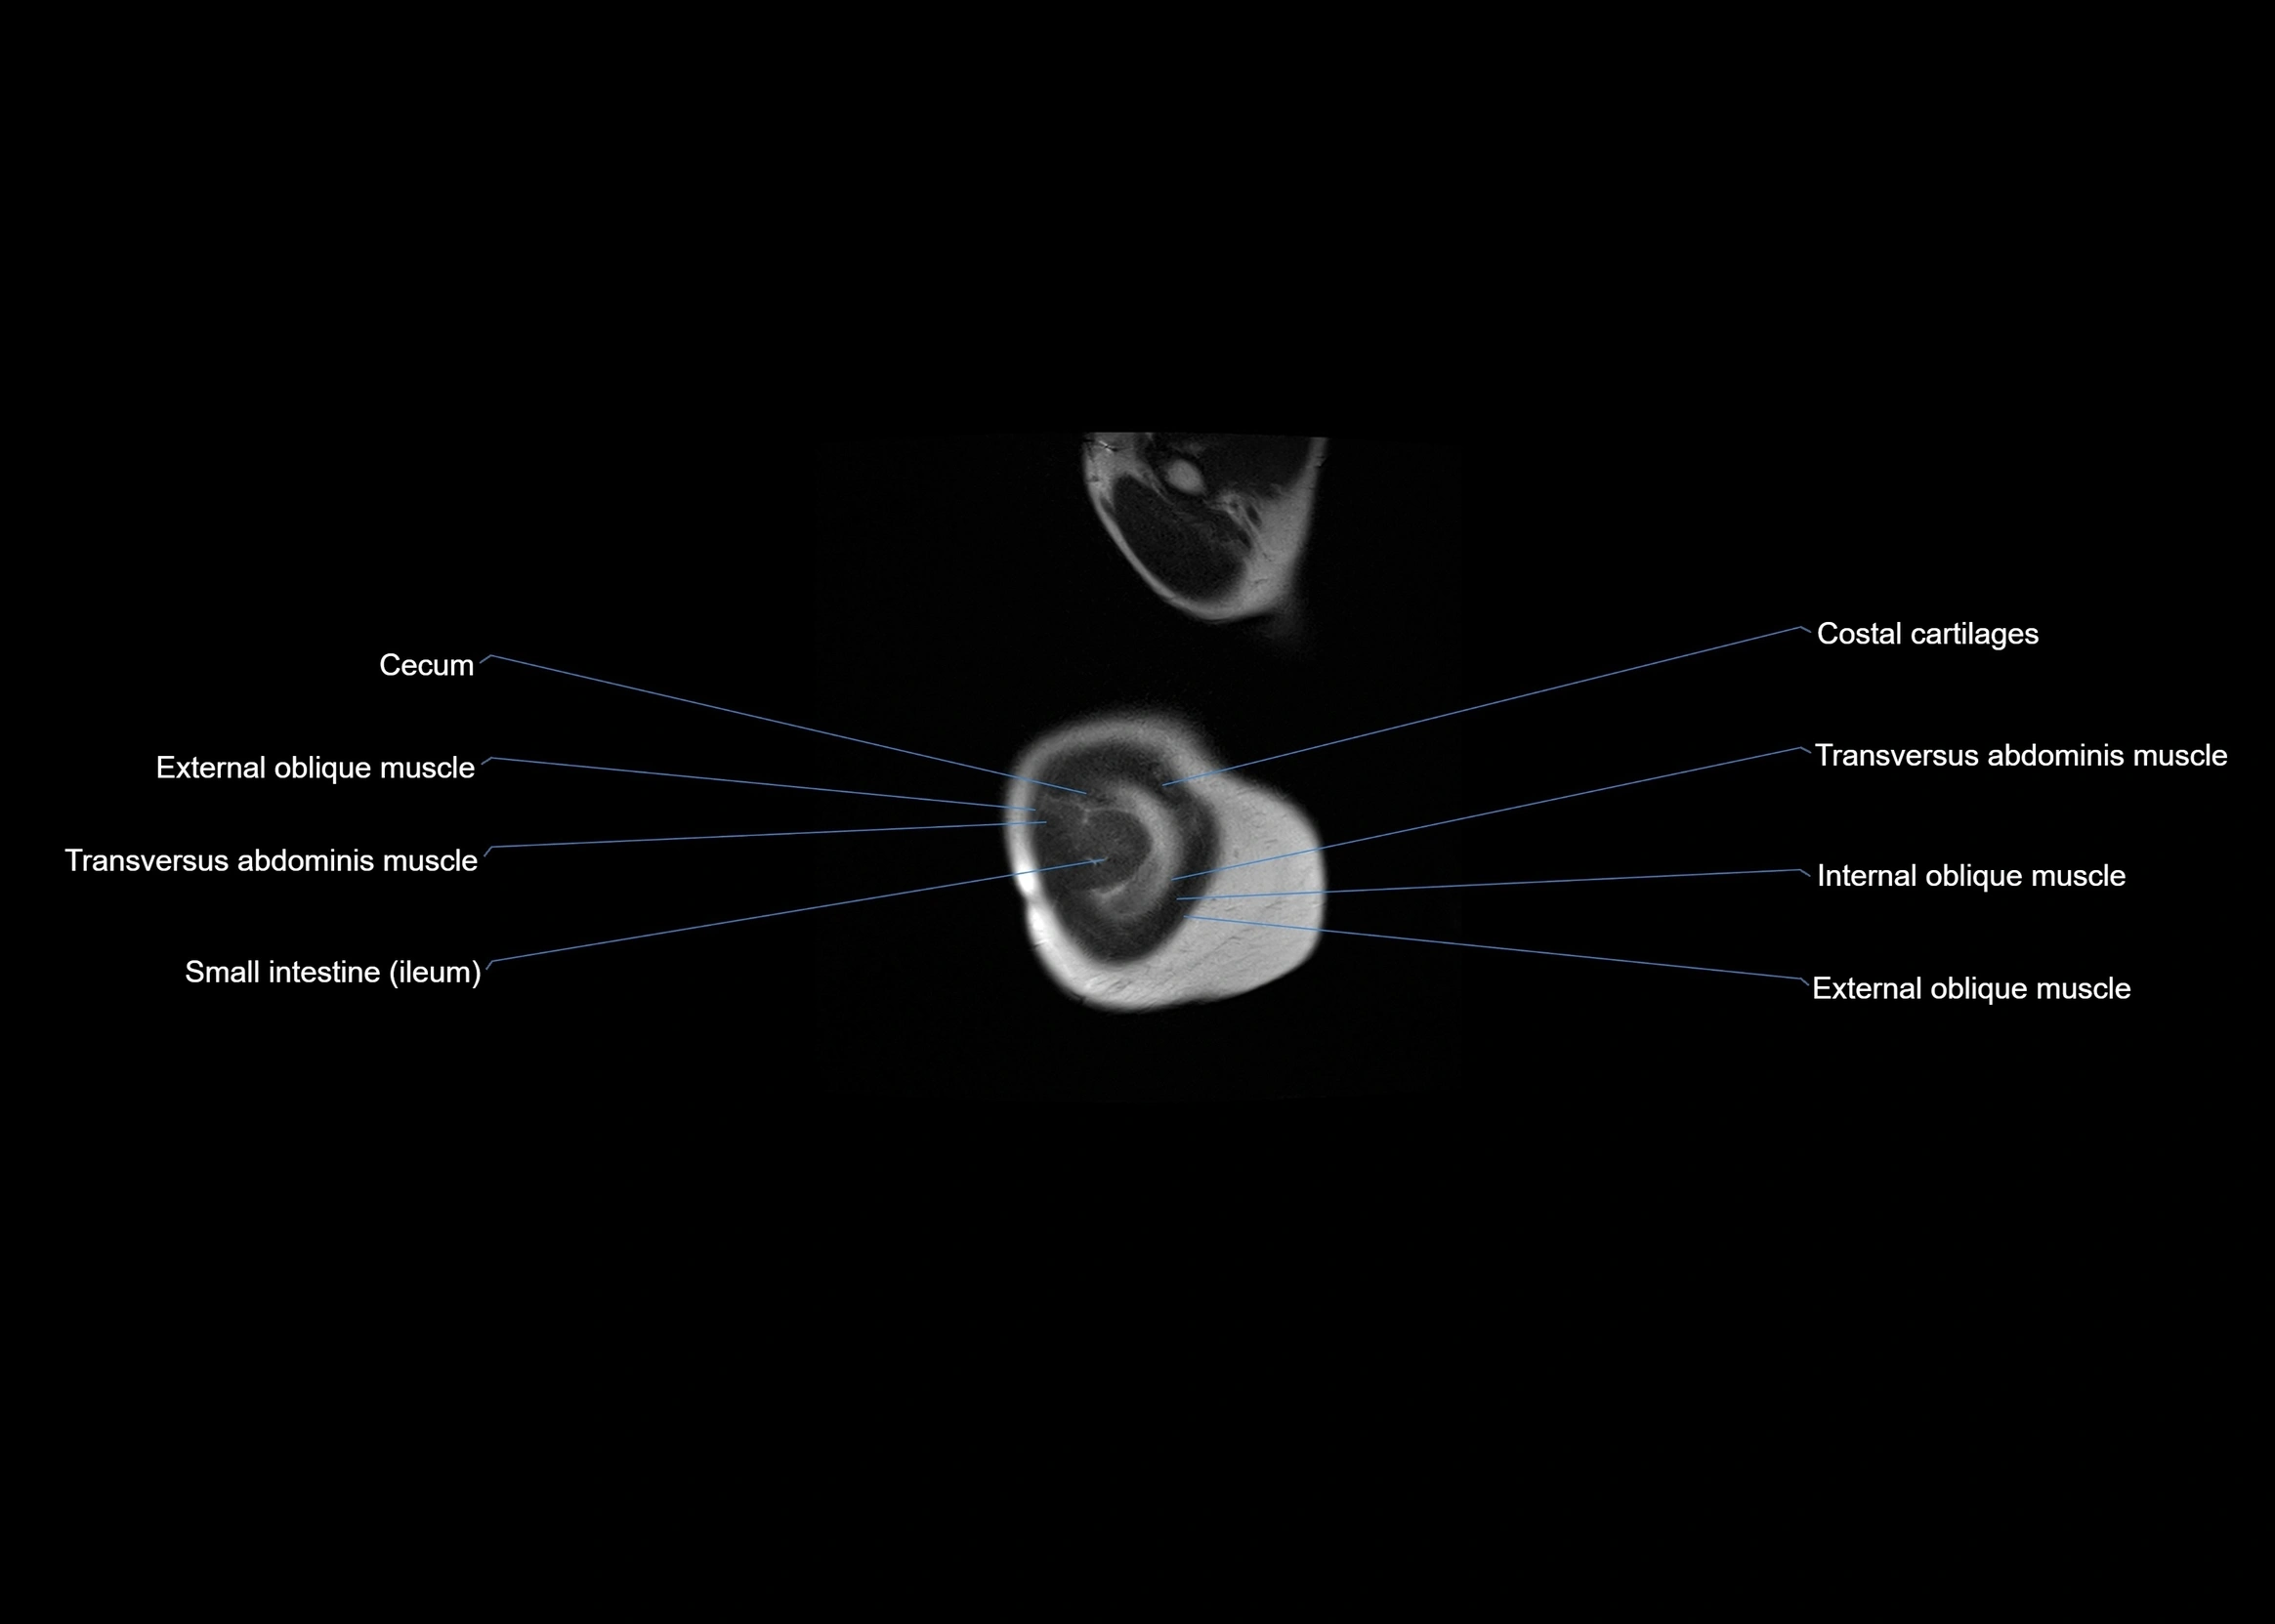

- Cecum

- External oblique muscle

- Ileum

- Internal oblique muscle

- Transversus abdominis muscle